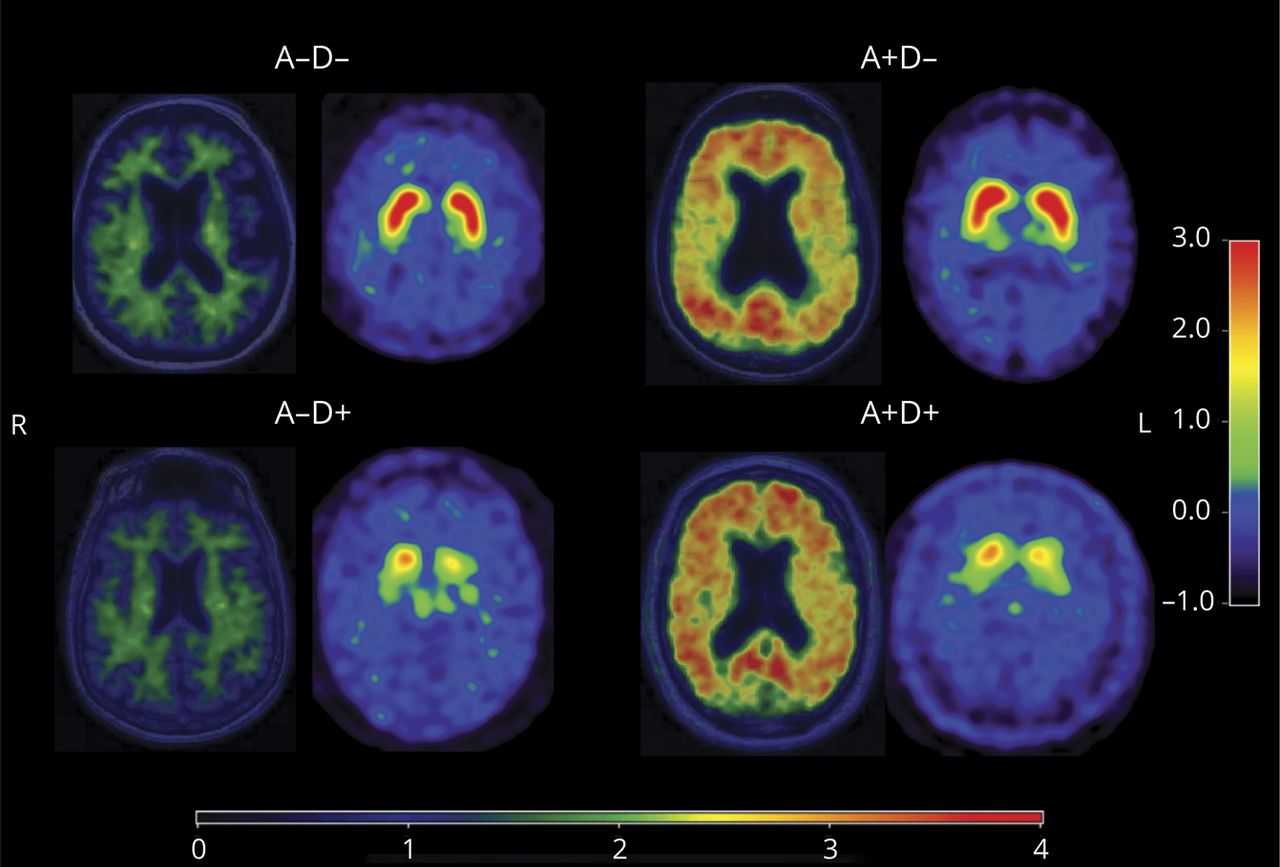

一分为二的β-amyloid宠物分布123年I-FP-CIT SPECT与单个数据点所示图1。−D +集团是最大的,占38.2%的患者MCI-LB (n = 13),后跟一个+ D + (n = 9)和D−−(n = 9),每一种都包括MCI-LB患者患者的26.5%。+ D−是最小的团体,其中包括8.8%的患者MCI-LB (n = 3)。β-amyloid宠物的形象和代表123年I-FP-CIT SPECT的4 A和D组所示图2。

散点图显示分布的轻度认知障碍患者路易小体(MCI-LB)象限的全球皮质匹兹堡化合物B(加以标准化率(SUVR)和壳核DaTQUANT吸收值z分数用彩色的点。参考线是1.48全球皮质加以SUVR和壳核DaTQUANT−0.82z分数。MCI-LB患者加以SUVR≥1.48确定异常β-amyloid宠物(+)。患者与壳核DaTQUANT MCI-LBz分数<−0.82确定异常123年I-FP-CIT SPECT (D +)。−−D =正常β-amyloid宠物和正常123年I-FP-CIT SPECT在灰色;+ D−=异常β-amyloid宠物但正常123年I-FP-CIT SPECT在蓝色;−D + =正常β-amyloid宠物但异常123年橙色,I-FP-CIT SPECT和+ D + =异常β-amyloid宠物和异常123年I-FP-CIT SPECT在绿色。